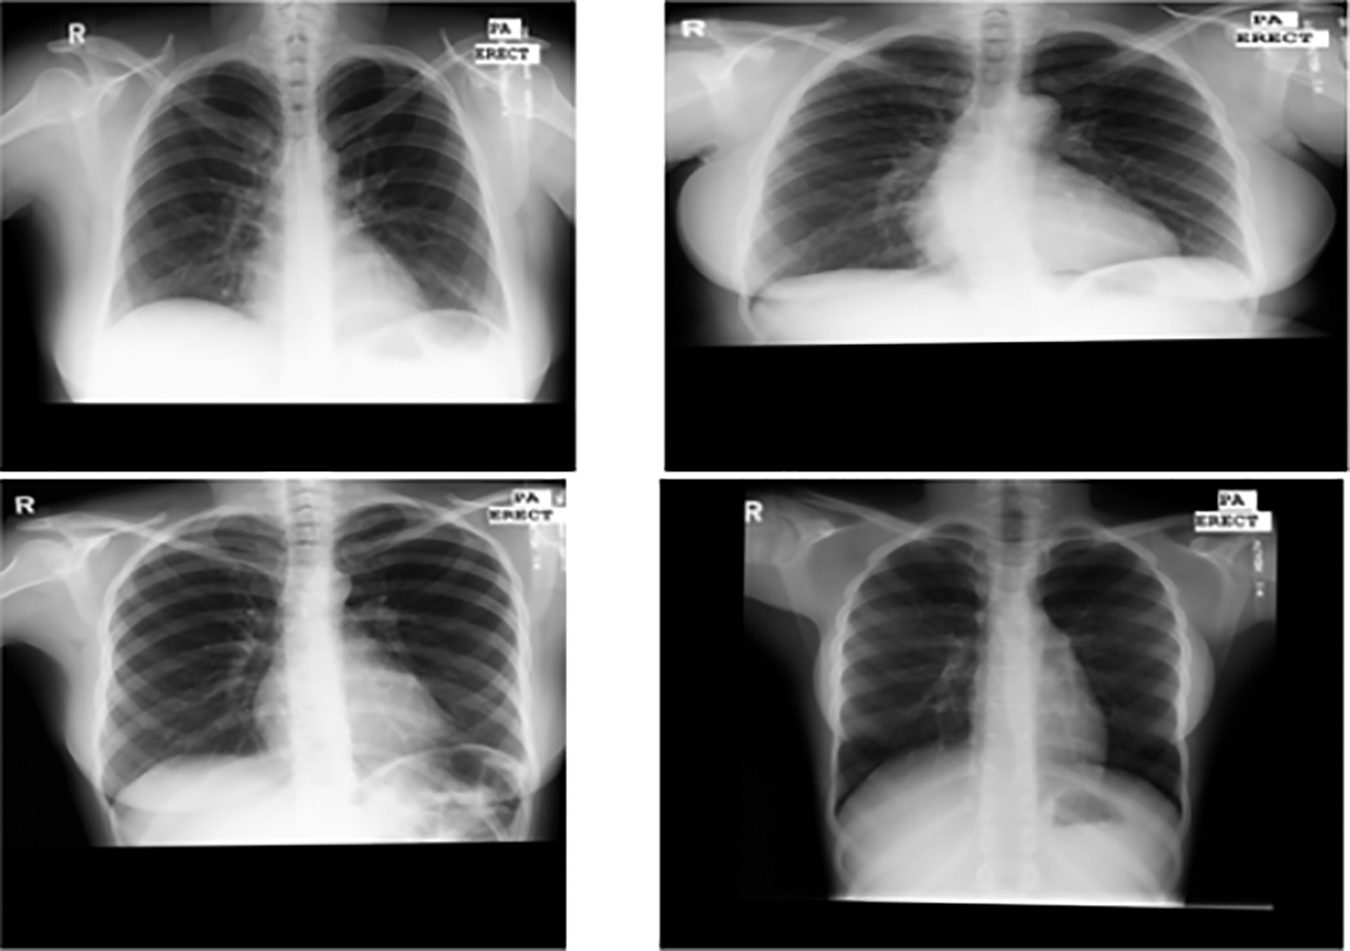

On open-source medical datasets, including the Ultrasonic Brachial Plexus, the Montgomery County Chest X-ray, and the BraTS18, we tested our suggested technique DeepGAN. The assessment findings and security analysis show that the proposed key generation network can create private keys with a high degree of security. The results are expected to show that it is successful in maintaining performance and privacy. This collection of 138 posterior-anterior radiographs includes 80 normal images and 58 images that are abnormal and show signs of tuberculosis as revealed in the figure. Every image is de-identified and offered in DICOM format. The package includes effusions and military patterns among the many abnormalities it covers. Fig. 5 shows the data distribution of normal and abnormal data in the dataset. Fig. 6 shows the sample x-ray images from the Montgomery county chest x-ray dataset. The X-ray pictures that are counted in this data set were obtained from the tuberculosis control program.

Figure 6: Montgomery county chest x-ray samples